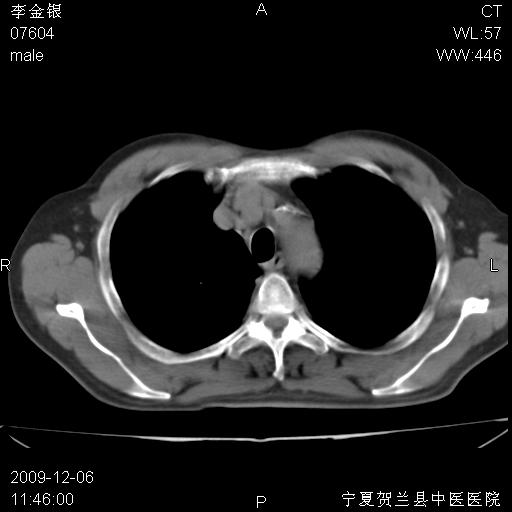

该病人 ,男,62岁,主因咳痰带血两天

考虑右肺中心型肺癌伴阻塞性肺炎及右肺门淋巴结转移,建议纤维支气管镜进一步检查。

支气管壁明显增厚 管腔狭窄,腔静脉后多个淋巴肿大,结合年龄病史考虑右肺上叶中央型肺癌并阻塞性肺炎

右肺上叶后段支气管阻塞,右上肺门占位,相应肺段阻塞性肺炎,右肺门有淋巴结肿大。诊断右肺上叶中心型肺癌,阻塞性肺肺炎、右肺门淋巴结转移。

符合中央型肺癌的ct表现并肺出血。但有一点腔静脉后有一钙化的淋巴结啊

右肺中心型肺癌伴阻塞性肺炎及右肺门与纵膈淋巴结转移很典型,可纤维支气管镜进一步检查

右侧中央型肺癌伴纵隔内淋巴结转移考虑。

考虑右侧中央型肺癌伴右肺上叶后段阻塞性炎症、肺不张、右肺门和纵隔淋巴结肿大。

右肺上叶中心型肺癌,阻塞性肺炎、右肺门和纵隔淋巴结转移。